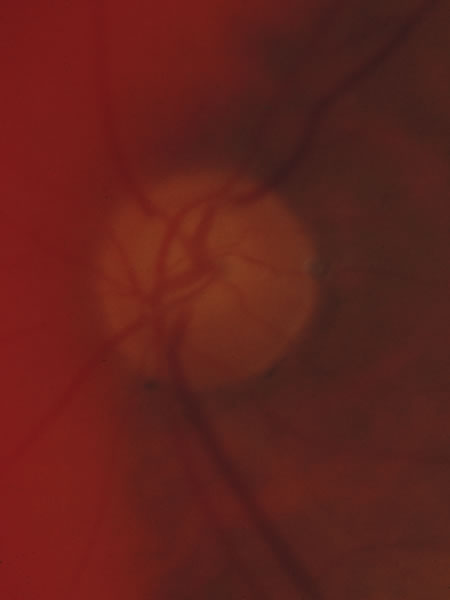

Fig. 34. Photograph of a normal left eye at a time when the right eye had an attack of anterior ischemic optic neuropathy.

Fig. 35. Same eye as Figure 34 during a subsequent attack of ischemic optic neuropathy.

Fig. 36. Same eye as in Figure 34 one year later, with atrophy but no excavation.